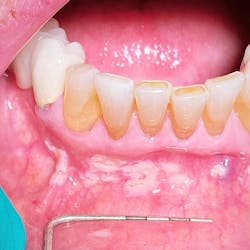

After five days, there were no changes. The patient shared that the lesion and area in general were very sensitive to acidic foods and painful overall when eating and functioning with day-to-day activities. He reported significant stress with his job due to travel/COVID-19 and the impact of things beyond his control.

The clinical exam revealed a large 12x9 mm lesion on the left side near the junction of the hard and soft palate. It was creamy white in color with irregular erythematous borders, most notably advanced in the oropharyngeal direction (figure 3).

Differentials include trauma, aphthous major, autoimmune disorders, and viral and nutritional deficiencies.

Furthermore, correlation has been found with the menstrual cycle, periods of stress and anxiety, and family history.1 In this particular case, the patient reported being under severe stress of late due to recent COVID-19 pandemic concerns with work and outside influences.